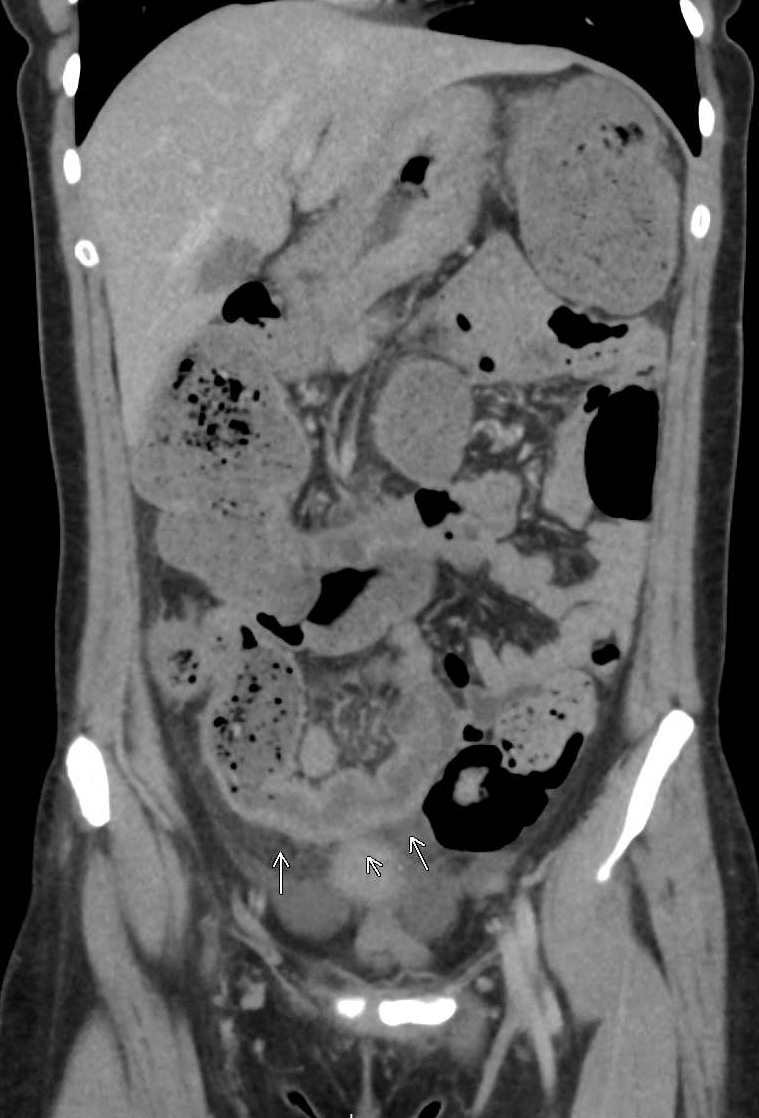

On hospital day 1, contrast-enhanced computed tomography of the abdomen and pelvis demonstrated circumferential wall thickening with surrounding fat stranding extending from the cecum to the mid-ascending colon, along with an abrupt transition at the splenic flexure and upstream colonic dilation (Figure 1A). Given concern for inflammatory bowel disease, bidirectional endoscopy was performed on hospital day 5. Esophagogastroduodenoscopy revealed obliterated gastric folds and diffusely congested mucosa, with limited retroflexion because of marked edema. Multiple large-cap cold forceps biopsies were obtained from the gastric body and antrum. Histopathologic examination demonstrated chronic inactive gastritis without evidence of Helicobacter pylori infection. Endoscopic ultrasound was not performed, and no submucosal sampling was obtained. Colonoscopy showed normal-appearing mucosa to 45 cm from the anal verge; beyond this point, the lumen was nearly obliterated by edematous, congested tissue, resulting in a nontraversable stricture (Figure 1B). Biopsies from the stricture demonstrated only nonspecific reactive changes.

Magnetic resonance enterography on hospital day 7 confirmed mural thickening and luminal narrowing of the descending colon with upstream distension, findings suggestive of a chronic stricture (Figure 1C). Moderate-volume pelvic ascites was also present, although there were no imaging features of portal hypertension. An extensive infectious and inflammatory evaluation, including stool cultures, ova and parasite examination, celiac serologies, tuberculosis testing, and serologic testing for Entamoeba histolytica, was unrevealing. Although ascites was present, no safe fluid pocket was available for diagnostic paracentesis. Because of progressive obstructive symptoms, worsening colonic dilation, and persistent diagnostic uncertainty despite extensive noninvasive evaluation, laparoscopic-assisted subtotal colectomy was performed on hospital day 8. Empiric immunosuppressive therapy for Crohn’s disease was deferred throughout the evaluation because of the absence of classic endoscopic features of inflammatory bowel disease and concern for an alternative diagnosis. Intraoperatively, multiple colonic strictures, adhesions involving the pancreas and spleen, mesenteric lymphadenopathy, and diffuse gastric wall thickening were identified.